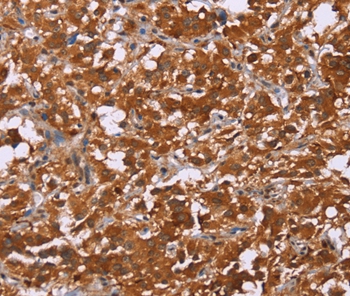

图片:

Immunohistochemical analysis of paraffin-embedded Human thyroid cancer tissue using #36401 at dilution 1/50.

Immunohistochemical analysis of paraffin-embedded Human brain tissue using #36401 at dilution 1/50.